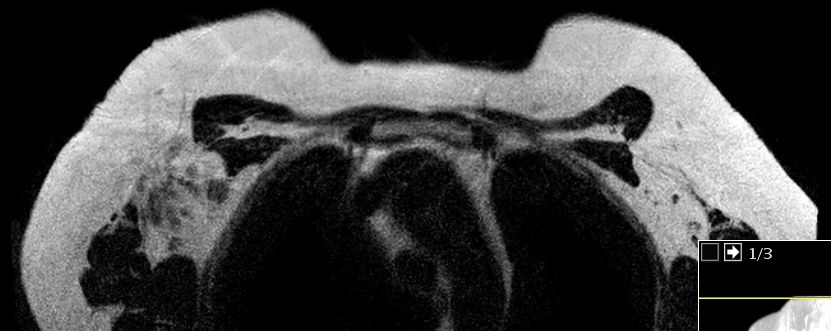

axilläre Metastasen ohne Primärtumor 51-jährige Frau mit axillärem Tastbefund. Mammographie und Sonographie o.B. Das MRT zeigt deutlich die axillären Lymphknoten.

MR im eThrive HR tra sense - Modus: Deutlich Darstellung einen 40mm großen Tumors.

Schnelle Anflutung und langsames Wash-Out sprechen für Malignität.